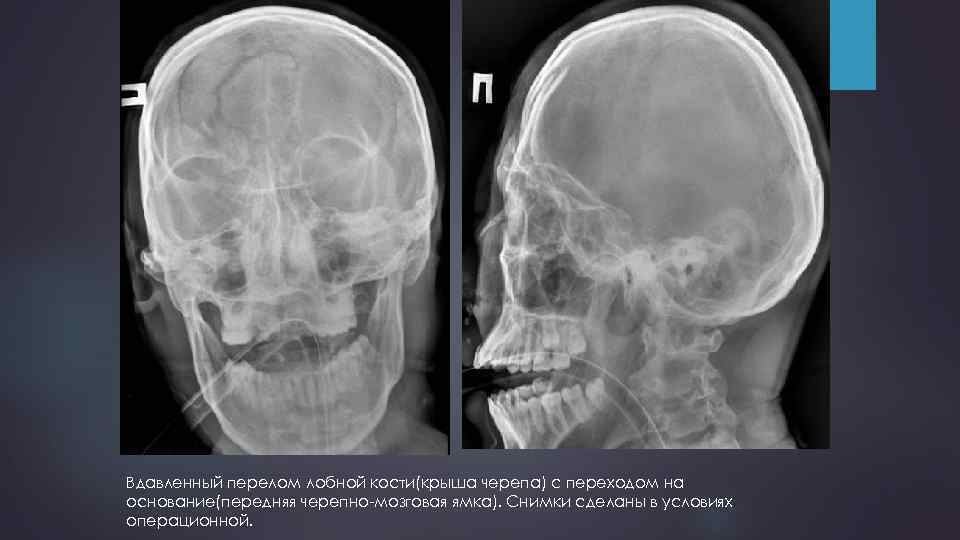

Вдавленный перелом лобной кости(крыша черепа) с переходом на основание(передняя черепно-мозговая ямка). Снимки сделаны в условиях операционной.